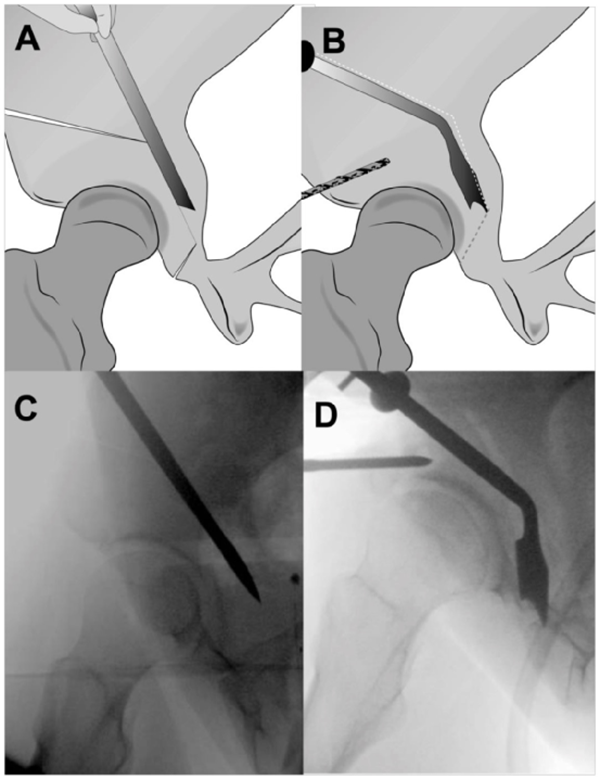

A.图示髋臼上截骨,其指向坐骨大切迹,在骨盆缘1cm处停止。B.坐骨截骨,沿骨盆內缘保留后柱截骨。

A.后柱截骨。B.成角骨刀截断残留连接处,截骨块充分游离。C.髂骨斜位透视图显示截骨线。D.游离截骨块